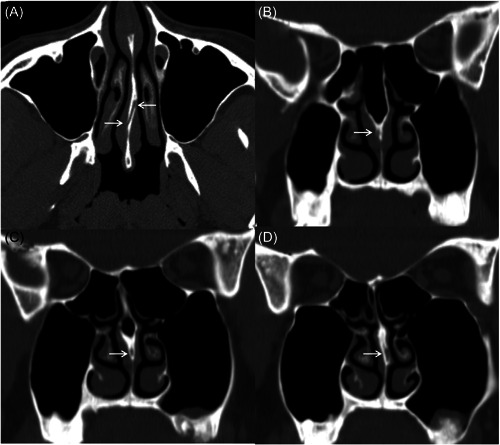

Case report: A 31-year-old female patient underwent suture removal 14 days after septoplasty and developed left-sided epistaxis 6 h after suture removal. To safely and effectively relieve the patient from epistaxis, the cauterization of the left PSA was performed under general anesthesia. However, 24 h after the first surgical hemostasis, the patient experienced epistaxis again in the right nasal cavity. We have reviewed the patient's sinus computed tomography again and found a rare variant of PSA, which is the right-sided PSA passing through a bony canal in the left-sided nasal septum.

Discussion: The variant of PSA well explained the failure of the first hemostatic surgery. Therefore, we again performed a cauterization of the right-sided PSA, after which the patient recovered and no further epistaxis occurred.